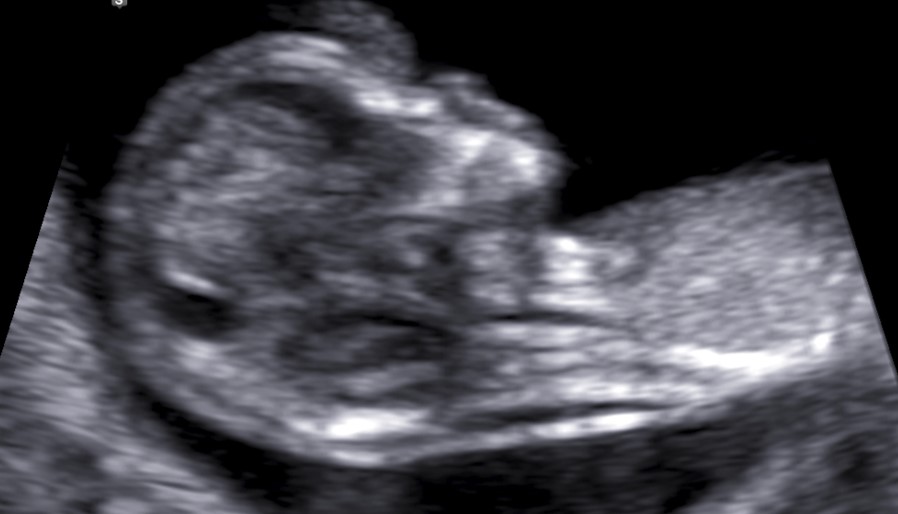

Korostunut niskaturvotus merkitsee, että sikiöllä on kohonnut riski kromosomi- tai rakennepoikkeavuuteen. Poikkeavuuden riski on sitä suurempi mitä paksumpi niskaturvotus on.

Korostunutta niskaturvotusta todetaan myös terveillä sikiöillä, eikä sen löytyminen vielä merkitse, että sikiöllä olisi todettu poikkeavuus. Kun sikiöllä todetaan korostunut niskaturvotus, tarjotaan raskaana olevan oman alueen sikiötutkimuksia tekevästä yksiköstä yksilöllistä neuvontaa niskaturvotukseen liittyvistä riskeistä sekä jatkotutkimusvaihtoehdoista.